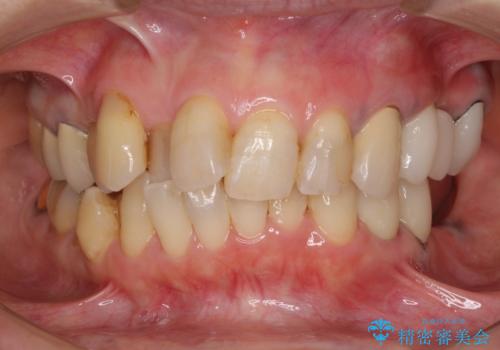

ノンクラスプデンチャー(金属止め具のない入れ歯)で左側の咬合回復

- 奥歯が痛いことを主訴にご来院された患者様です。入院してしまい、治療を2年間放置してしまったとのことでした。

左上は、抜歯とブリッジ治療を行いました(抜歯前に医師と対診)。

左下は、現在も抗がん治療を続けているため、観血的処置(インプラントなどの外科)はなるべく避けたいとのことで入れ歯を希望されました。それに伴い、入れ歯を支える歯のクラウンやりかえも行いました。

患者様はインプラント等の外科処置は希望されなかったため、セラミックと義歯で治療を行いました。

義歯を製作する際は、支えとなる歯の治療も同時に行うことで、義歯の製作が容易になります。

今回もそのように製作したところ、適合がよく安定のよい義歯になりました。患者様本人も使っていて全く痛くないとのことで、追加の調整もなく使用して頂いてます。患者様には、大変満足して頂きました。